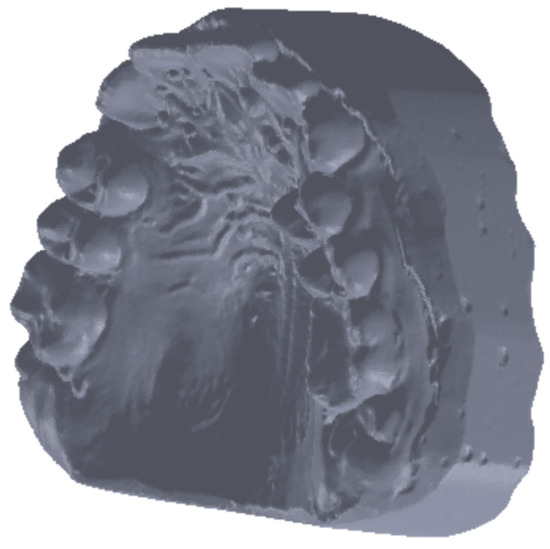

To obtain the final model, 30 successive scans were performed. Then, we obtained the final model of the scan operation. Figure 5 shows the common point cloud of the upper and lower images, which represents the raw, unprocessed model of the scanned maxillary.

Finally, we obtained a closed final surface, as shown in Figure 6.

Figure 5. Scanned image of the maxillary arch.

Figure 6. Perfectly closed surface obtained after the filling operation.